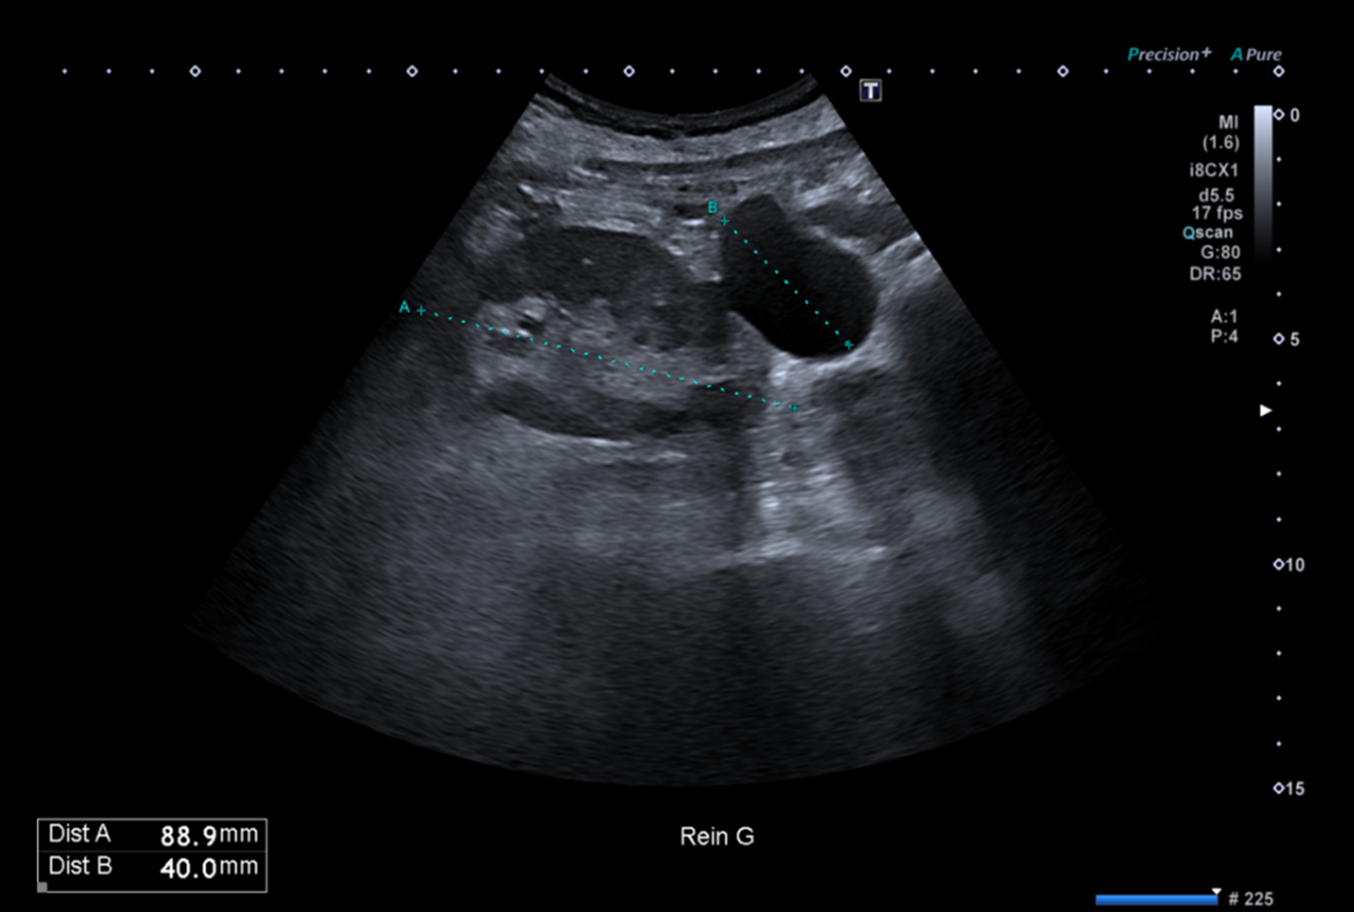

Pour illustrer cela, à quoi vous fait penser cette formation anéchogène située au pôle inférieur du rein gauche sur cette coupe d’échographie abdominale réalisée dans un contexte de surveillance de cirrhose post infection VHC chez une patiente de 74 ans ?

Celui qui se contente de cette seule coupe répondra très probablement kyste simple.

Ces nouvelles coupes (faisant apparaitre la rate, le doppler couleur et le doppler pulsé), montrent alors non pas un kyste rénal mais des volumineuses veines péri spléniques correspondant à des voies de dérivations spléno-rénales témoignant d’une hypertension portale probablement liée à la cirrhose sous-jacente.

Il est donc nécessaire de compléter son examen par une recherche d’autres signes d’hypertension portale notamment la présence d’ascite ou toute autre dérivation veineuse digestive (recanalisation de la VO, varices porto-portales, dilatation de la VMS et/ou dilatation des veines gastriques, varices mésentérique-caves (difficilement visibles en échographie-Doppler) ou la présence de varices porto-caves).